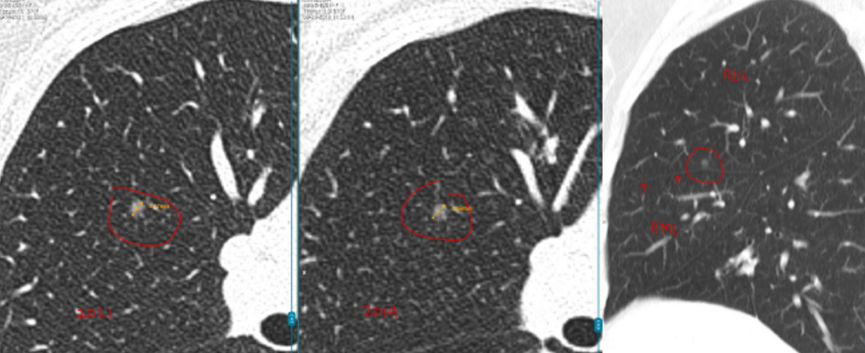

具体来看,右肺有一个磨玻璃结节(约4mm),左肺还有两个实性结节(约5mm、3mm)。

之后的4年里,这3枚小结节都没有什么变化,这让她逐渐放下心来。

然而在随后的一次复查中,CT结果显示磨玻璃结节“密度略微增加”,而且又新出现了一枚3mm的小结节。

“先看左肺这两枚实性结节,它们在这几年一直很稳定,没有明显增大,形态也没有变化。像这类稳定超过3年的小实性结节,良性可能性超过了99%。从片子上看,它们更像是肺部之前因为旧损伤留下的痕迹。”L教授说。

关于右肺的4mm磨玻璃结节,L教授对比了新旧影像,并不认为它在恶化。

“这一枚,是您现在担心的,对吗?因为报告里提到它的密度比以前稍微高了一点。但从影像上看,这种变化还是非常轻微的,目前还没有达到让我们怀疑它正在明显恶化的程度。它确实值得继续随访,但至少以现在这个状态,还谈不上需要立刻处理,更不意味着已经朝着癌的方向快速发展。”L教授说。

关于右肺新出现的那枚大约3mm的磨玻璃结节,L教授同样为林女士进行了详细解释。

他指出,很多人一听到出现新发结节,马上会非常紧张,觉得可能是冒出了不好的东西。其实不是这样。

“像这么小、这么淡的磨玻璃结节,在临床上很常见,很多时候更像是一过性的炎性反应,可能和轻微感染甚至短期肺部状态变化有关。有些结节过一段时间复查,自己就消失了。所以对这枚结节,我目前更倾向于把它看作一个温和的、需要观察的信号,而不是一个必须马上干预的问题。”L教授说。

L教授总结道:“总体来看,您现在这4枚结节都还很小,而且没有哪一枚表现出必须马上手术或活检的证据。左肺两枚实性结节长期稳定,右肺原有的磨玻璃结节虽然密度略有变化,但幅度很小,新发的3mm磨玻璃结节也更像炎性改变。换句话说,它们都还没有到‘该切的时候’。现阶段继续按计划随访,是安全的,也是更合理的做法。”